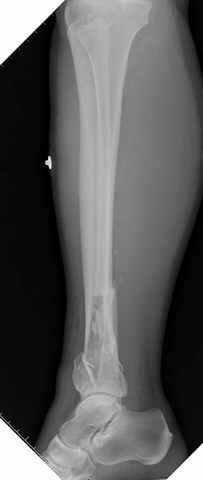

На снимках варианты фиксации малоберцовой:

№ 6-11 при pilon percutaneus fixation

DK> № 6-11 при pilon percutaneus fixation

А если без? Результат был бы хуже?